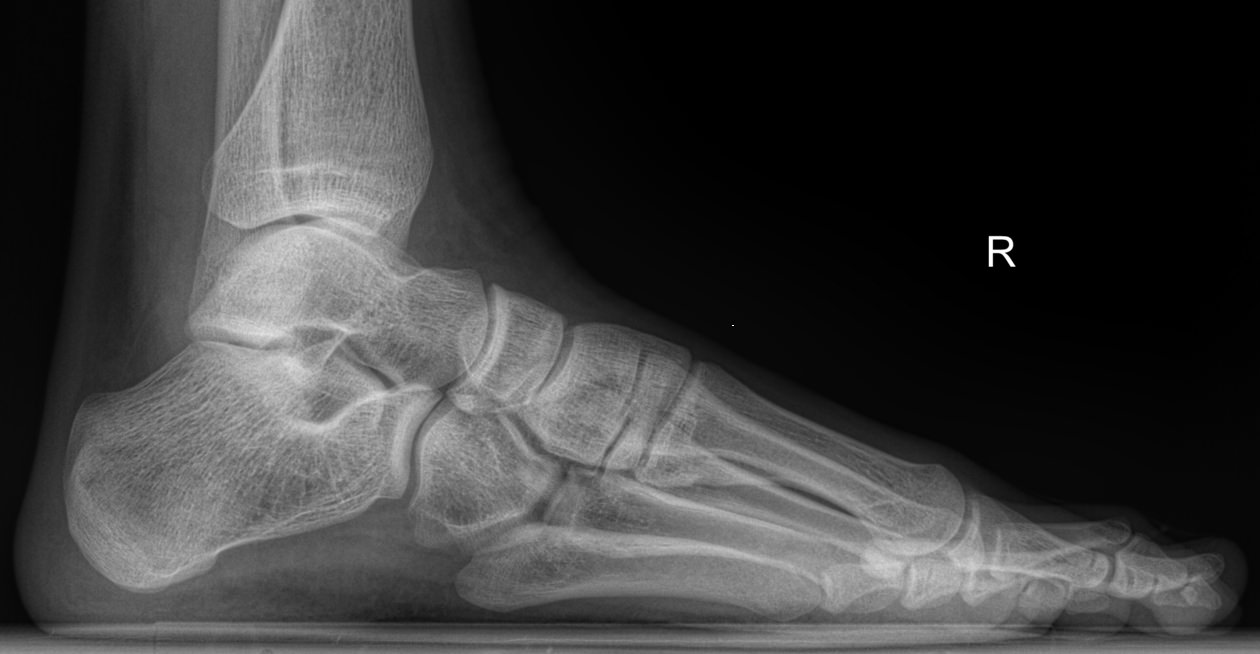

В качестве диагностической процедуры для выявления плоскостопия часто используют рентген. Прицельное исследование стопы позволяет увидеть изменения в ее строении, а также вычислить угол и высоту свода стопы, показатели которых используются для установления стадии болезни.

На снимке будут отчетливо видны:

• Кости предплюсны;

• Наложенные друг на друга кости плюсны;

• Травмы, в том числе застарелые;

• Патологические изменения видимых суставов;

• Опухоли.

Рассчитывается высота и угол свода стопы и соответствующая им степень плоскостопия.

Никакой подготовки не требуется. Пациент оголяет ногу ниже колена и ставит ее на пластину детектора. При этом вес тела переносится на исследуемую ногу. Жизненно важные органы закрываются защитным фартуком. Съемка выполняется в боковой проекции и идет 1-2 секунды, во время которых важно не шевелиться.